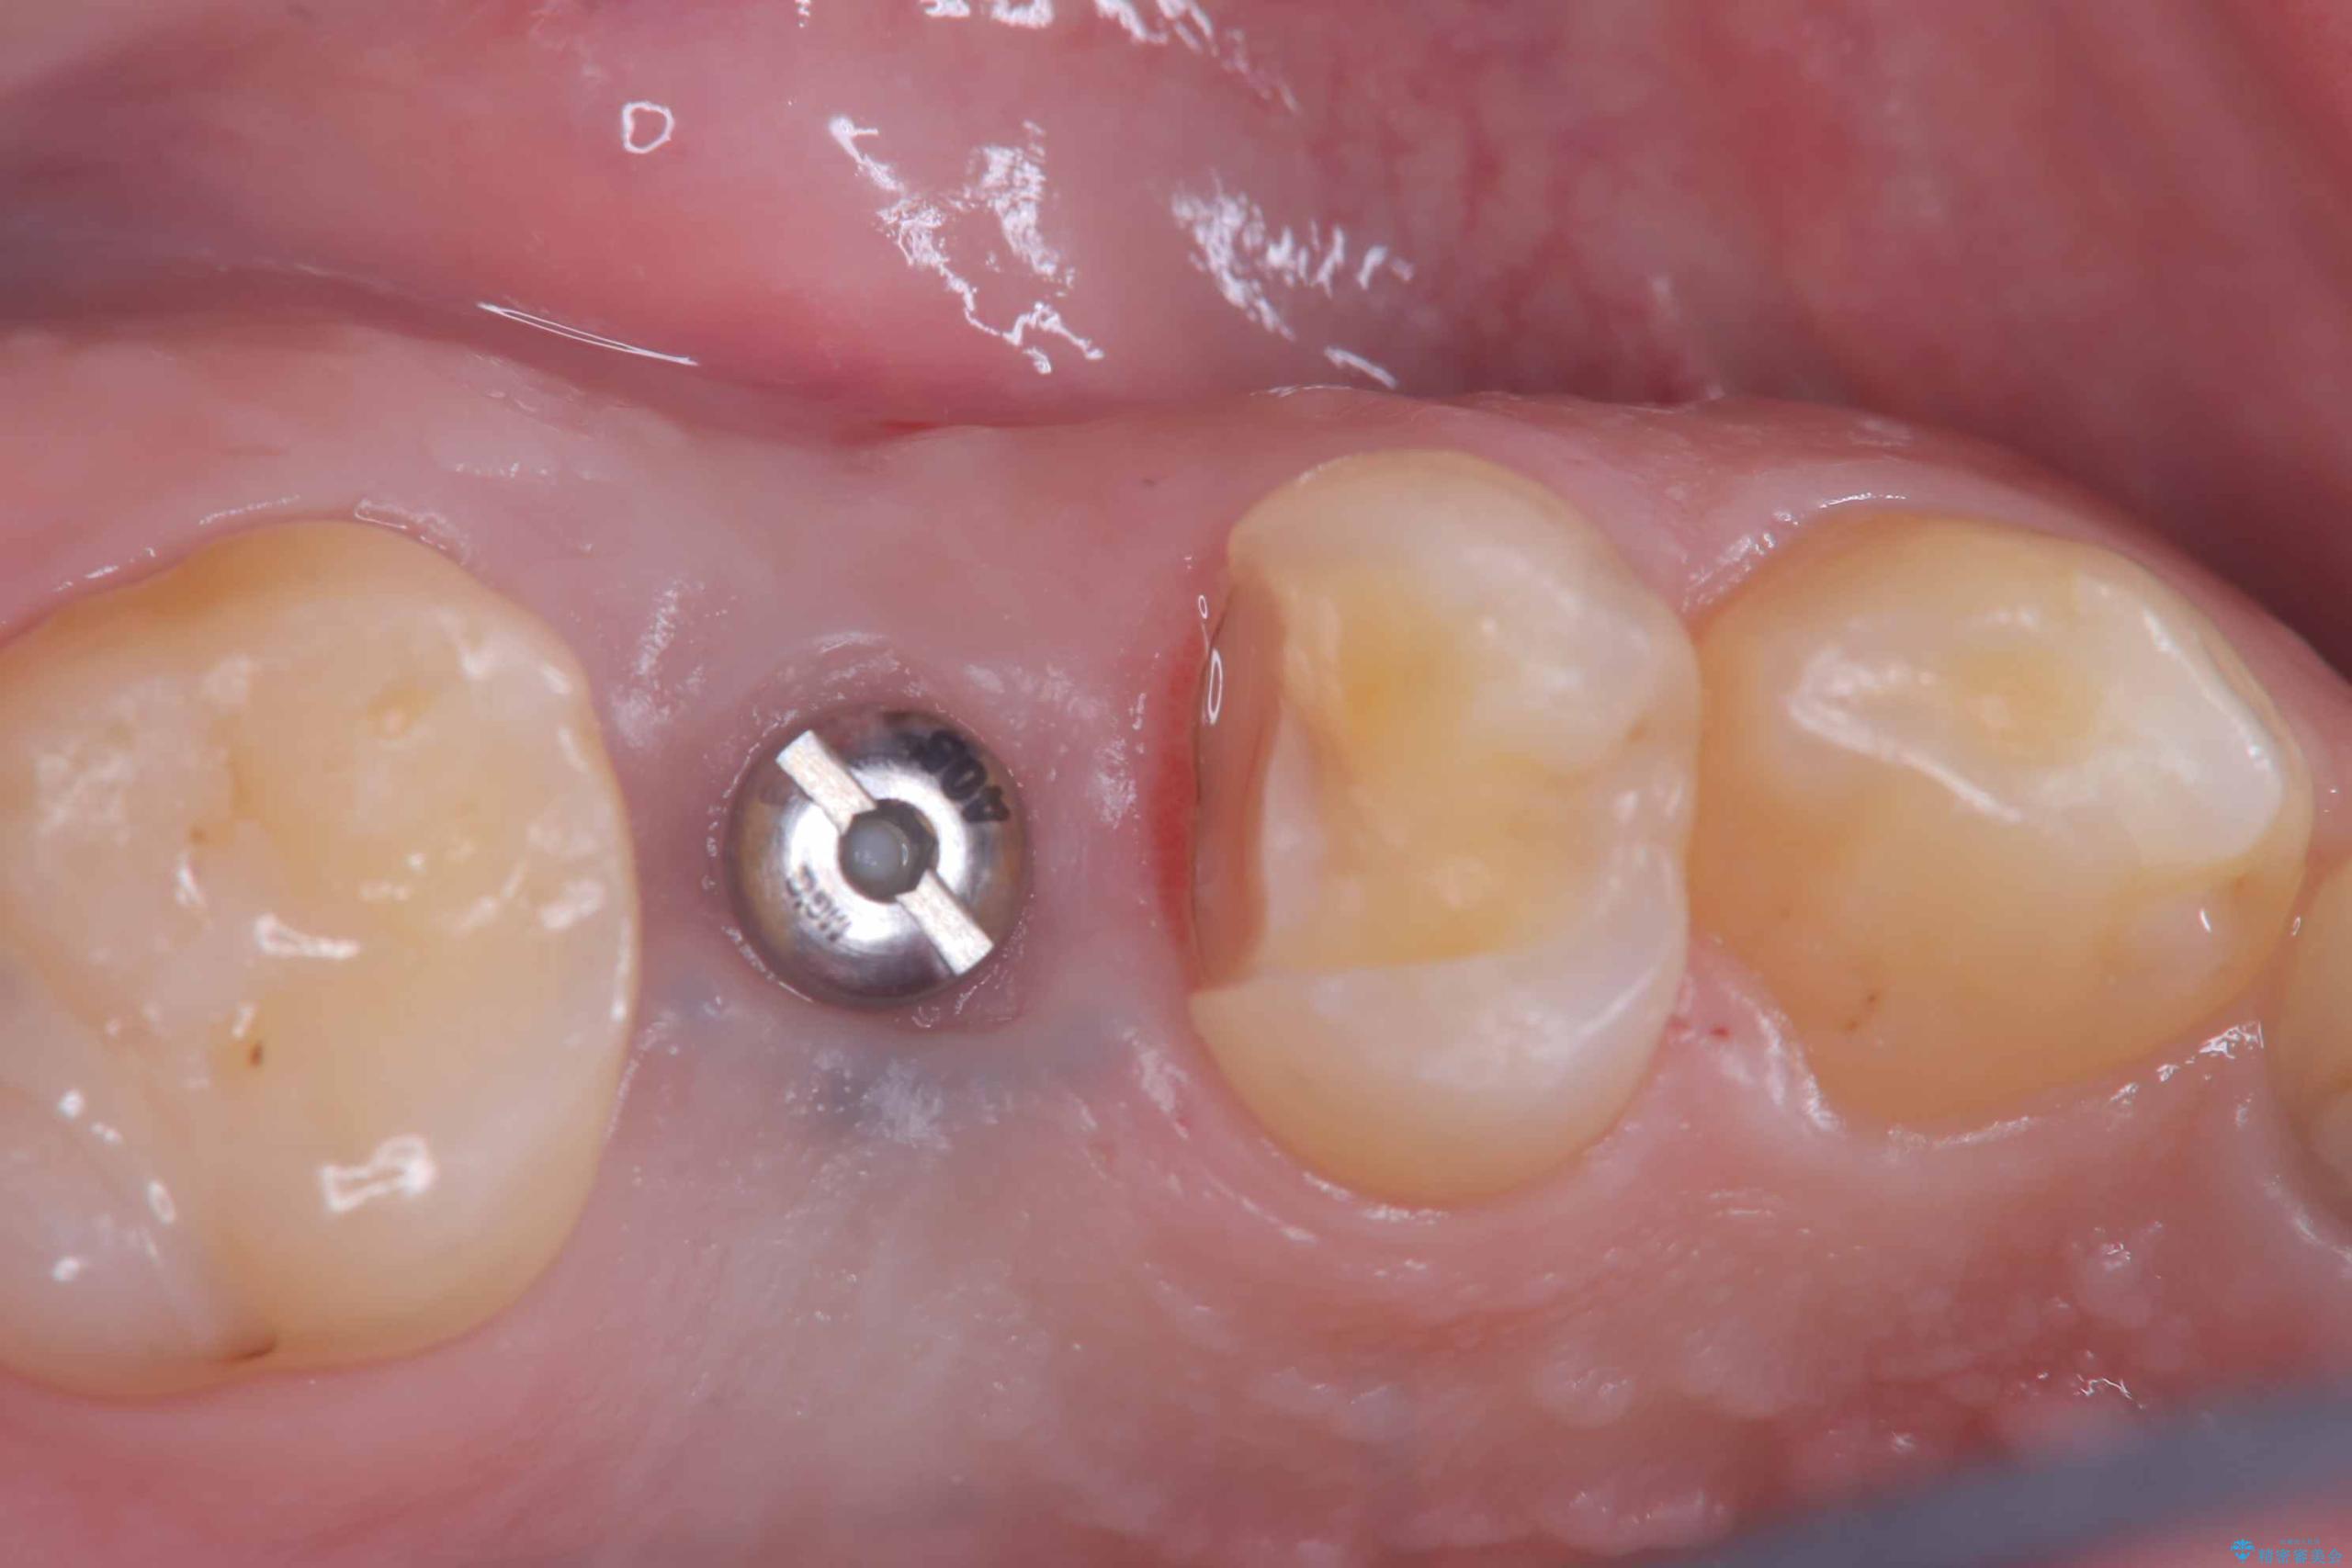

インプラントはインプラント周囲炎になりにくいスクリュータイプを使用しています。

従来のインプラント治療では、オペを二回に分けることが主流でしたが今は1回のオペで治療を終える事が出来るようになりました。

インプラントと骨が強度にくっつくように骨密度を上げながらドリリングを行っているのと、患者様の骨の状態に合わせてインプラントの形態を選ぶことで可能となっています。

オペの回数を最小にする事で患者様の治療への負担が減り、治療期間も従来の治療より大幅に短くする事が可能です。